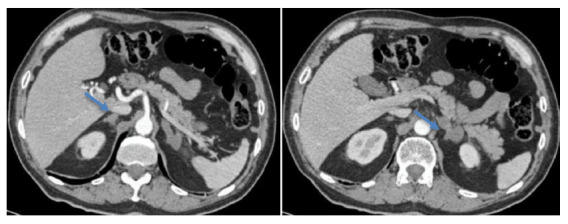

全身真菌病,如隐球菌病,主要影响肺部和中枢神经系统;然而,累及其他器官,如肾上腺,是罕见的。这已经在真菌源性原发性肾上腺功能不全(PAI)的一些病例中得到了描述,这与高死亡率有关。我们提出的情况下,65岁的免疫能力男子谁提出的临床表现肾上腺功能不全。生化检查证实PAI,腹部断层扫描显示双肾上腺增生,主要在左侧。患者行左肾上腺切除术,病理检查发现肉芽肿及真菌结构与隐球菌相容,患者接受激素替代治疗及抗真菌治疗,预后良好。PAI的鉴别诊断应考虑隐球菌性肾上腺炎,特别是在有相关流行病学史的情况下,及时治疗是改善预后的关键。

Systemic mycoses, such as cryptococcosis, mainly affect the lungs and central nervous system; however, involvement of other organs, such as the adrenal glands, is rare. This has been described in some cases of primary adrenal insufficiency (PAI) of fungal origin, which are associated with high mortality. We present the case of a 65-year-old immunocompetent man who presented clinical manifestations of adrenal insufficiency. Biochemical tests confirmed PAI, and abdominal tomography revealed hyperplasia of both adrenal glands, predominantly on the left side. Left adrenalectomy was performed, and pathological examination identified granulomas and fungal structures compatible with Cryptococcus spp. The patient received hormone replacement therapy and antifungal treatment, with favorable outcome. Cryptococcal adrenalitis should be considered in the differential diagnosis of PAI, particularly in the presence of relevant epidemiological history, and timely treatment is key to improving prognosis.